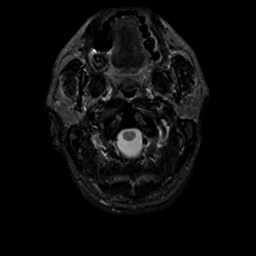

MR Study #20 October 6, 1991 -- Slice #0

[Home][Help][Clinical][Tour 1][Tour 2] Slice 0